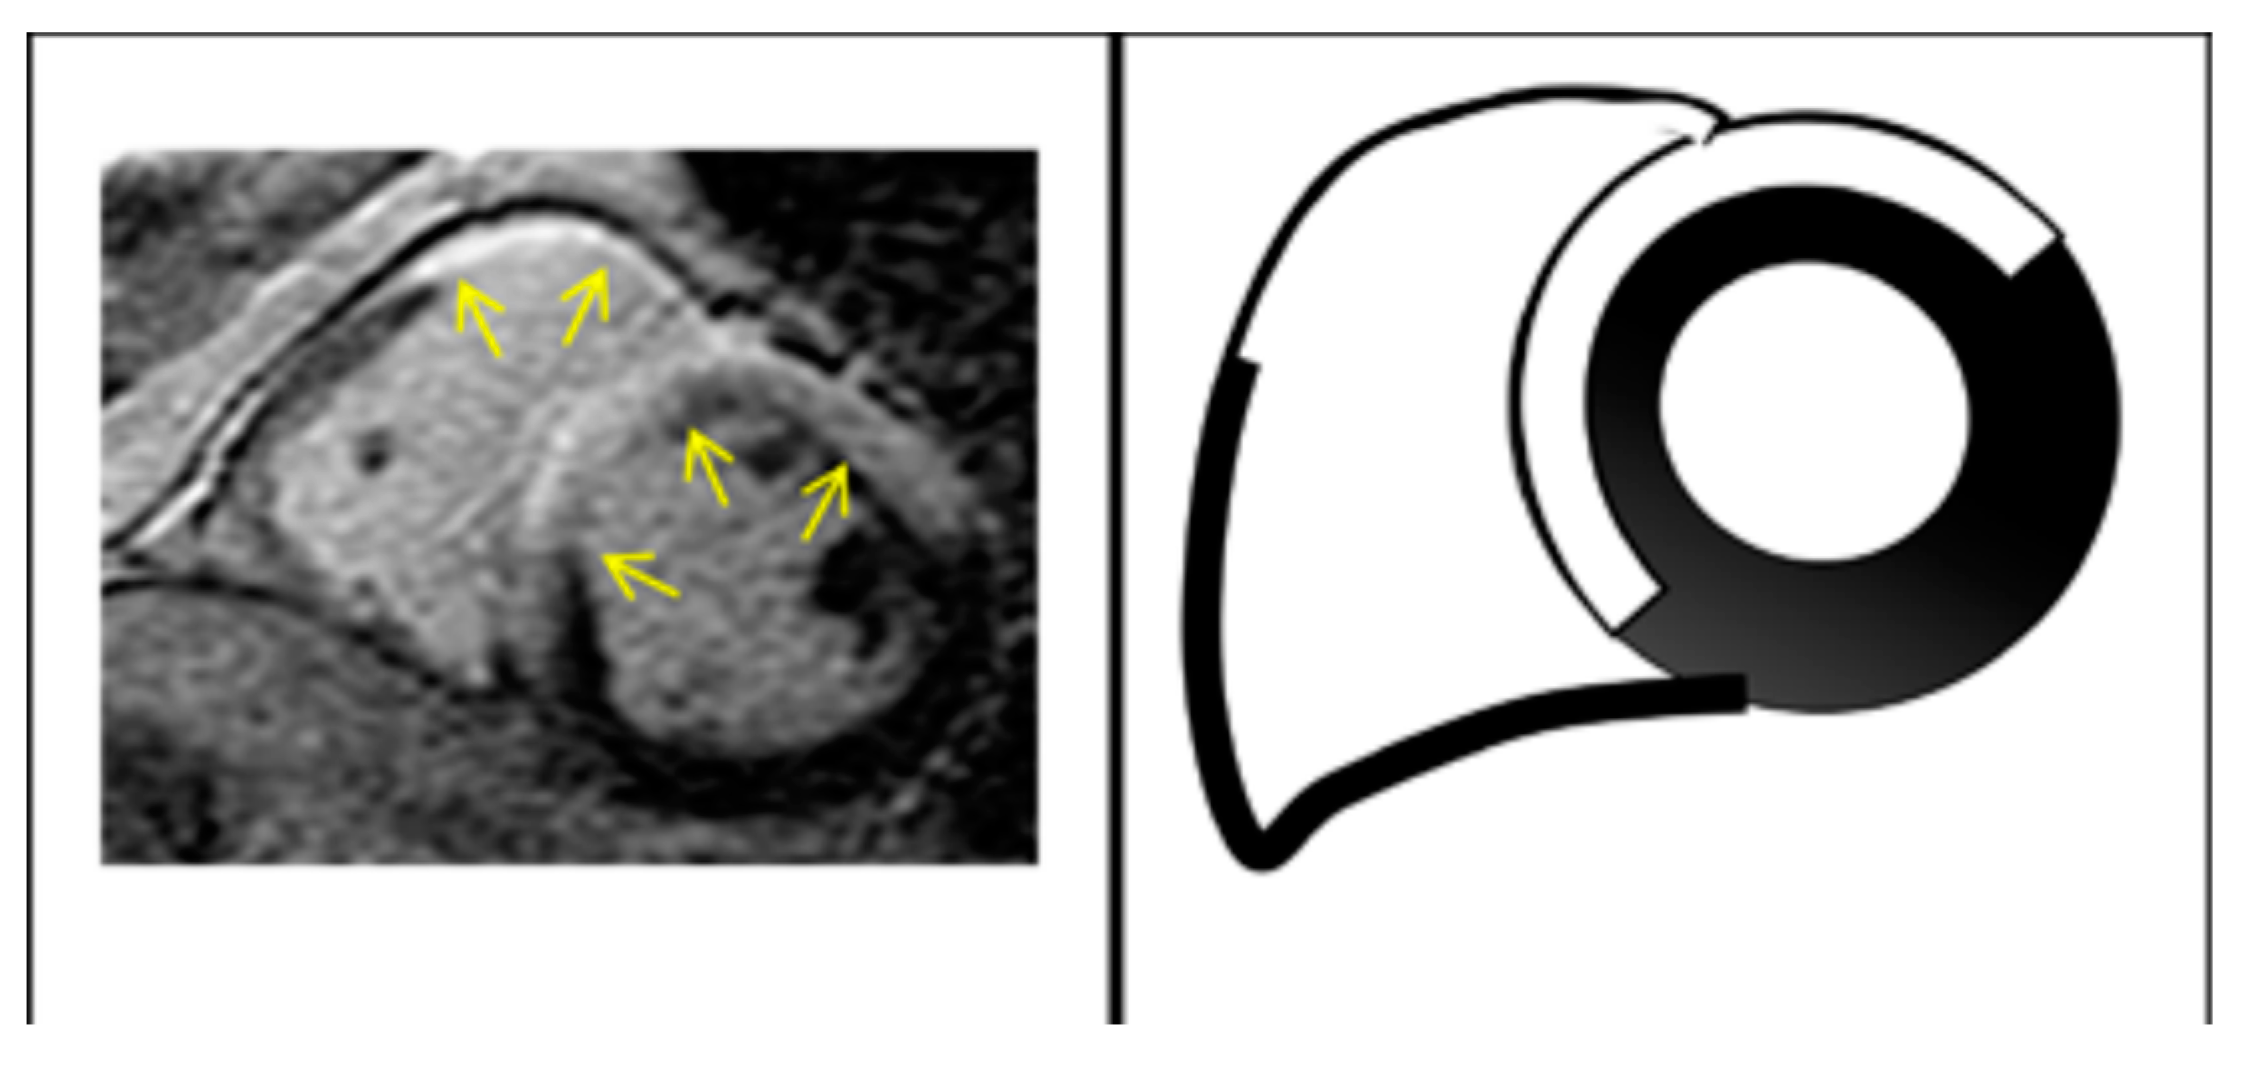

2.2. Cardiac Magnetic Resonance

- He, J.; Xu, J.; Li, G.; Zhou, D.; Li, S.; Zhuang, B.; Chen, X.; Duan, X.; Li, L.; Fan, X.; et al. Arrhythmogenic Left Ventricular Cardiomyopathy: A Clinical and CMR Study. Sci. Rep. 2020, 10, 533. [Google Scholar] [CrossRef] [PubMed]

- Monda, E.; Rubino, M.; Palmiero, G.; Verrillo, F.; Lioncino, M.; Diana, G.; Cirillo, A.; Fusco, A.; Dongiglio, F.; Caiazza, M.; et al. Multimodality Imaging in Arrhythmogenic Left Ventricular Cardiomyopathy. J. Clin. Med. 2023, 12, 1568. [Google Scholar] [CrossRef]